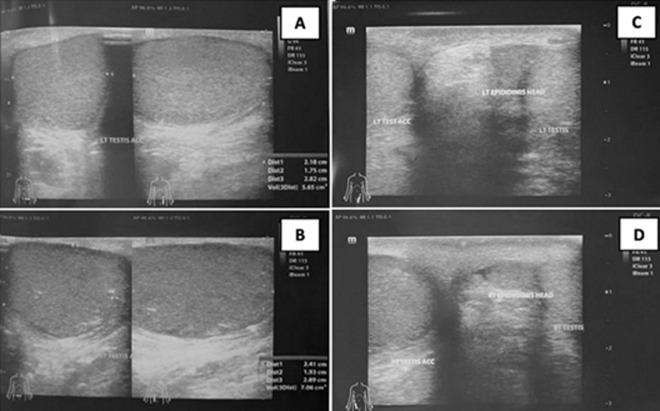

Bilateral scrotal masses may present as polyorchidism or benign neoplasms. Epidermoid cysts (ECs) are common benign cutaneous lesions that are characterized by encapsulated sebaceous cysts containing keratin. These cysts can undergo complications such as ruptures, infections, or daughter cyst formation. A 29-year-old male presented with an asymptomatic scrotal mass. On physical examination, intrascrotal masses were palpated superior to each testis. An ultrasonographic evaluation revealed that the two masses were discrete and located superior to the right and left testis, respectively. The parenchymal echogenicity of these lesions was comparable to that of normal testicular parenchyma. Under the clinical impression of benign scrotal lesions, the provisional diagnosis was of bilateral testicular masses due to polyorchidism. Surgical intervention involved the complete excision of both masses. The subsequent histopathological examination revealed the definitive diagnosis of ECs. This case illustrates that despite the advantages of Doppler imaging, ultrasonography may yield less accurate results than histopathological findings.

双侧阴囊肿块可能表现为多睾症或良性肿瘤。表皮样囊肿(ECs)是常见的良性皮肤病变,其特征是含有角蛋白的包膜皮脂腺囊肿。这些囊肿可能会出现破裂、感染或形成子囊肿等并发症。一名29岁男性出现无症状阴囊肿块。体格检查时,在每个睾丸上方可触及阴囊内肿块。超声检查显示这两个肿块是分开的,分别位于右侧和左侧睾丸上方。这些病变的实质回声与正常睾丸实质相当。在良性阴囊病变的临床印象下,初步诊断为双侧睾丸肿块由多睾症引起。手术干预包括完整切除两个肿块。随后的组织病理学检查确诊为表皮样囊肿。该病例表明,尽管多普勒成像有优势,但超声检查的结果可能不如组织病理学检查准确。